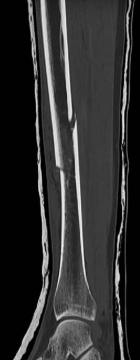

Standard orthogonal radiographs (anteroposterior and lateral) are insufficient for evaluating tibial fractures with suspected plafond extension. A dedicated computed tomography (CT) scan of the ankle with coronal, sagittal, and 3D reconstructions is mandatory.

Image

The CT scan serves several critical functions. First, it identifies the exact location and orientation of the articular split. Second, it dictates the trajectory of the independent articular lag screws, ensuring they are placed perfectly perpendicular to the fracture plane. Third, and perhaps most importantly, it allows the surgeon to map the safe zones for these lag screws so they do not obstruct the planned path of the intramedullary nail.